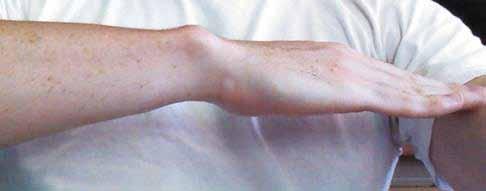

Dupuytrens kontraktur, populärt kallad ”vikingasjukan” kan numera behandlas med injektioner i stället för en, i många fall, ganska oviss operation. Metoden är ny sedan i höstas, så än så länge är det oklart hur den fungerar på lång sikt.

UEn av dem är Hans Bergvall, pensionerad sjuksköterska. Han är helt övertygad om me todens förträfflighet. Och han talar av erfaren het. Hans har nämligen lidit av krokiga fingrar i båda händerna. Den ena har han fått opere rad, den andra injicerad.

Han berättar livligt om smärtorna efter ope rationen, och en titt på den handen bär syn för sägen. Breda operationsärr löper från ett finger långt in på handen. Så visar han upp den andra handen. Det enda som egentligen syns är en liten förtjockning där fingret lämnar handen.

-Det här är en fantastisk metod, menar Hans, både hälsoekonomiskt och praktiskt.

-I stället för sjukhus och en dyr operation gjordes det här på två besök polikliniskt.

Första dagen fick Hans ett antal injektioner i bindväven i handen.

-Det gjorde rejält ont, medger Hans. Man har ju mycket nerver i handen.

Behandlingen var över på några minuter. Dag två fick Hans först en lokalbedövning som skulle verka i 20 minuter:

-Under tiden träffade jag en arbetsterapeut som berättade hur jag skulle träna handen ef teråt, berättar Hans förtjust, mycket imponerad av att ingen tid gick till spillo på sjukhuset.

Hans Bergvall är mycket nöjd med den nya metoden.

-Sedan fick jag order att titta bort, läkaren ryckte till i fingret, som var helt rakt när jag tittade igen.

-Allt var bra, bortsett från att huden i handen sprack på två ställen, men det läkte ihop på helt normalt sätt.

I dag är Hans överlycklig över att han kan göra sådant han inte kunde förut, arbeta i träd-

gården, rensa ogräs, byta blöja på barnbarnen etc.

En liten förtjockning på ringfingrets insida är det enda synliga tecknet efter behandlingen.